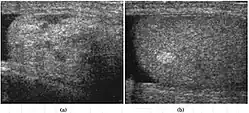

The incidence of infertility is decreased if surgical orchiopexy is carried out before the 1–3 years but the risk of malignancy does not change. Because of the superficial location of the inguinal canal in children, sonography of undescended testes should be performed with a high frequency transducer. At ultrasound, the undescended testis usually appears small, less echogenic than the contralateral normal testis and usually located in the inguinal region [Fig. 29]. With color Doppler, the vascularity of the undescended testis is poor.

Fig. 29. Undescended testis. (a) Normal testis in the scrotum. (b) Atrophic and decreased echogenicity of the contralateral testis of the same patient seen in the inguinal region.